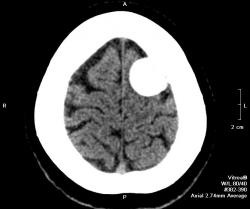

Полностью обызвествленная менингиома теменной области (красная стрелка). В прилегающей кости узурация (зеленые стрелки) и небольшой гиперостоз в виде клюва (голубая стрелка). Небольшой масс-эффект - крыша левого бокового желудочка поддавлена (желтая стрелка), субарахноидальные щели слева немного уже, чем справа. Перифокального отека нет - признак доброкачественности образования. Отек при менингиоме может развиться при очень больших размерах образования или при малигнизации. Пациентка жалуется на головные боли. На снимках черепа ничего необычного нет.

Опухоль доброкачественная, растет медленно годами, иногда десятилетиями. Но убирать ее надо, так как она уже вызывает сдавление головного мозга. Если ее убрать полность, а локализация, я думаю, позволяет, то рецидива не будет. Одно "но", опухоль богато васкуляризирована, во время удаления бывают кровопотери, кровоизлияния в ложе удаленной опухоли, что может привести к ишемии в окружающих тканях мозга, т. е. неврологический дефицит может оказаться, в результате этих осложнений, несколько большим, чем до операции. Но это не всегда происходит. Рецедивы происходят только при неполном удалении. Иногда менингиомы озлокачествляются и тогда рост их ускоряется, появляется перифокальный отек, участки распада, прорастание прилегающей кости.